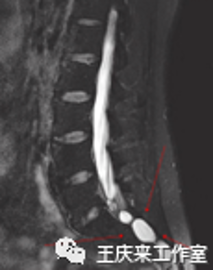

臨床中,“尾骨痛”的診斷主要依靠病史和體格檢查。患者以骶尾部疼痛為主要表現,并通常在坐姿不正確或坐姿站起時明顯,按壓或觸及尾骨局部出現疼痛。直腸指檢檢查對于本病的診斷具有重要意義,可用于判斷局部組織壓力敏感反應、尾骨活動度等情況。注意必要時須完善影像學檢查如CT、磁共振等以鑒別診斷。